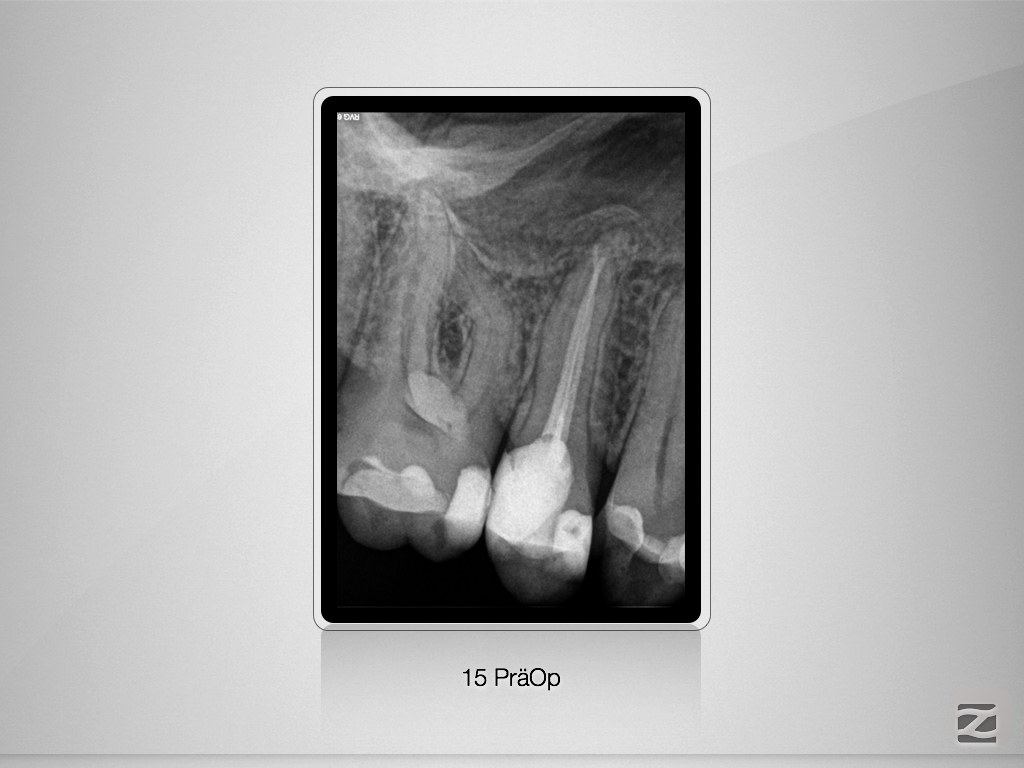

Immer schön skeptisch bleiben, …